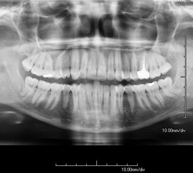

Técnica mediante la cual, utilizando rayos X, se obtienen imágenes del cráneo para su estudio. Indicaciones: traumatismo, cierre precoz de suturas craneales. - RX Senos Paranasales

Técnica mediante la cual, utilizando rayos X, se obtienen imágenes de los senos paranasales para su estudio. Indicaciones: dificultad respiratoria nasal, tos crónica, cefalea, mucosidad. - RX ATM (Articulación Temporo-Mandibular)

Técnica mediante la cual, utilizando rayos X, se obtienen imágenes de la mandíbula para su estudio. Indicaciones: traumatismo, anomalías congénitas. - RX Laringe